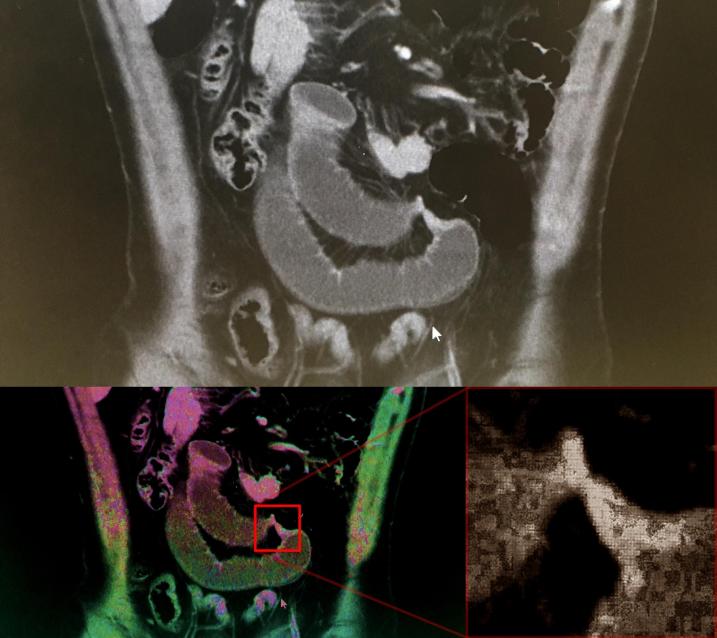

At my post-op checkup this week I was able to look at the CT scan (3D x-ray) that they took when I was rushed into hospital. The two large grey stubby tubes are the expanded sections of my small intestine, and the strangulated part connecting them is very easy to see:

I was marvelling at the technology and knowledge that is behind this kind of x-ray imaging, and wondering how I could connect it to noise in order to justify making a blog post about it, ha! The answer is Quantum Noise…

It should be evident that such phenomena as quantum noise are entirely natural and to be expected. The statistically random variations that cause many types of visual and audio noise are not inherently problematic, and indeed when aggregated en masse noise helps provide the repeatable predictability of many systemic characteristics and behaviours. Noise performs necessary functions, and brings particular aesthetics along for the ride too (I quite like the grainy effect). Visual noise becomes problematic depending on the nature, extent, context, and need for clarity and precision of knowledge within specific applications. In the case of my CT scan, there was obviously no need for the effects of quantum noise (and other forms of visual noise that come from the imaging equipment, computer screen composition, etc) to be any more diluted in order to ascertain where and what the basic problem was. But they couldn’t tell until they got inside me that there was no necrosis, and that it was the colon’s surrounding fat tissue that was the specific culprit. As medical technology advances, and ways to mitigate or bypass the detrimental effects of high-dosage radiation are discovered, I am sure that current CT scan imaging will look very primitive in decades or centuries to come.